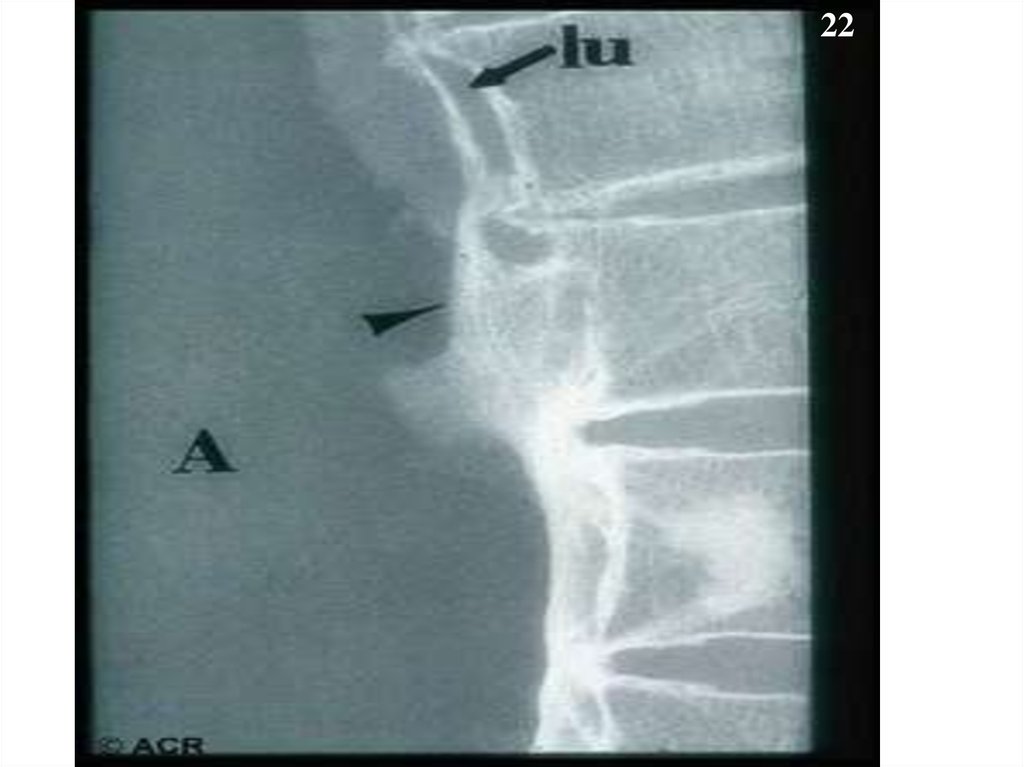

22.

22